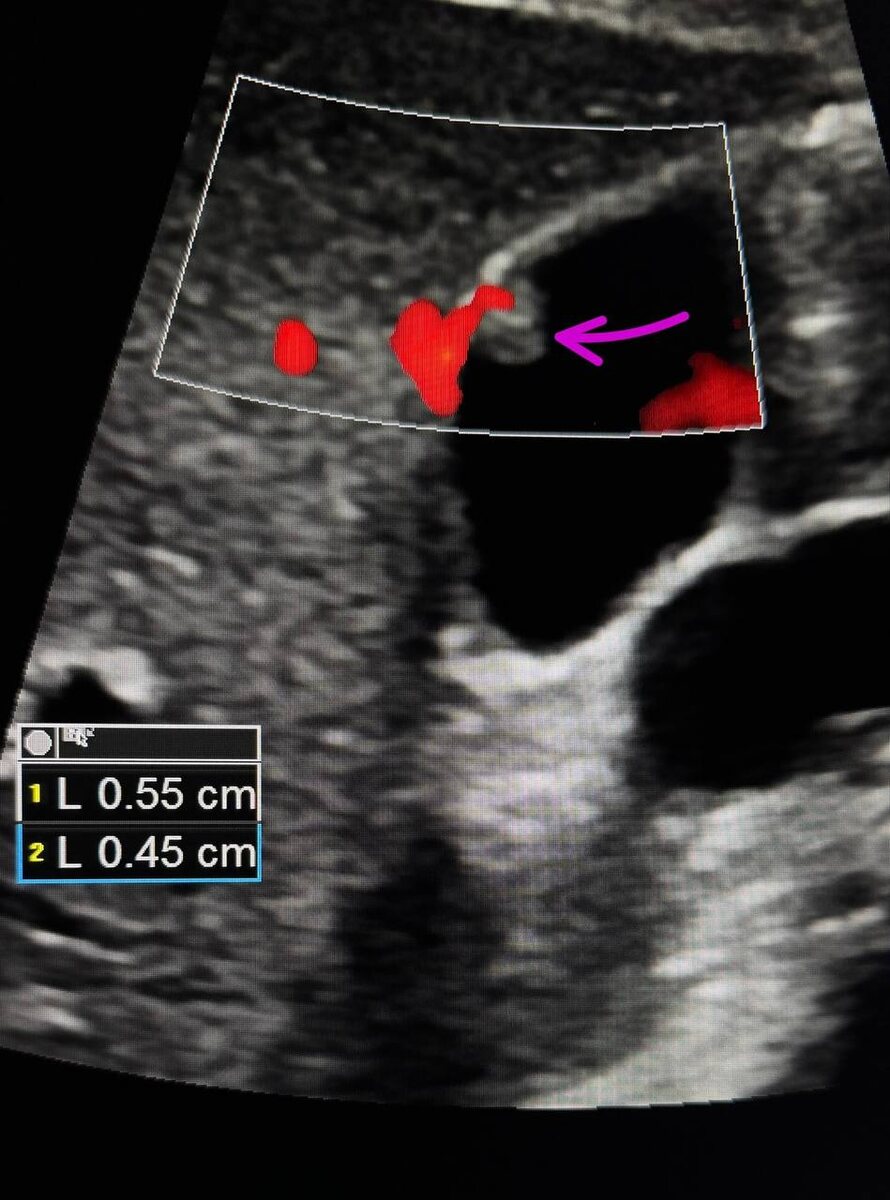

*для врачебной аудитории: К признакам неопластических полипов относятся: единая дольчатая поверхность, сосудистое ядро, гипоэхогенный полип и гипоэхогенные очаги, размер полипа более 1 см.

Частота встречаемости пристеночных образований желчного пузыря на УЗИ составляет до 10% при рутинном скринингом исследовании органов брюшной полости. Для диагностики желчного пузыря метод УЗИ является наиболее чувствительным среди прочих (чувствительность метода составляет 72,2-83%), например, при компьютерной томографии полипы могут быть пропущены.

Благодаря современным методам УЗИ удаётся определить истинный полип (аденоматозный полип) желчного пузыря или ложный (холестериновое отложение стенки). Кроме холестериновых и истинных полипов, данные методы позволяют выявить ещё один тип доброкачественных образований желчного пузыря. Это воспалительные полипы - локальные изменения стенки желчного пузыря, формирующиеся на фоне его воспалительных процессов.

Для принятия решения о дальнейшей тактике ведения пациента необходимо оценивать следующие показатели. Во - первых, обычно учитывается наличие факторов риска (указаны ниже в тексте). Во-вторых, оценивается размер полипа, наличие или отсутствие кровотока в его области, есть ли утолщение стенки желчного пузыря, рост полипа в динамике и другие критерии. Это важно для того чтобы оценить необходимость своевременной консультации хирурга для обсуждения проведения возможной операции.